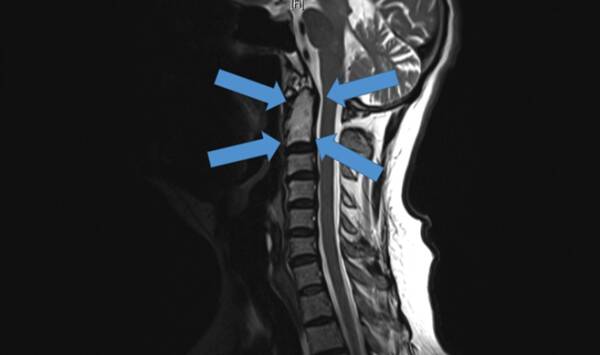

2015年底,世界首例采用3D打印椎骨植入物

脊柱行業(yè)也是未來醫(yī)療器械市場,最新發(fā)展趨勢之一。通過3D打印技術(shù),來達到創(chuàng)新產(chǎn)品的目的,該技術(shù)可以促進骨骼向內(nèi)生長,并改善植入物對脊柱骨的固定,縮短制造流程,提高患者滿意度,從而在某些情況下更具成本效益。

例如,Medtronic鈦金屬3D打印平臺——TiONIC技術(shù)。使用激光方法制造具有增強表面紋理的植入物。Artic-L是該公司使用TiONIC技術(shù)制造的第一款金屬植入物??晒┩饪漆t(yī)生在脊柱手術(shù)中使用。還有K2MLamellar,同樣采用鈦制造3D脊柱植入物。使用金屬3D打印技術(shù)特有的優(yōu)勢之一,可實現(xiàn)曾經(jīng)被傳統(tǒng)制造技術(shù),認為不切實際的結(jié)構(gòu)。